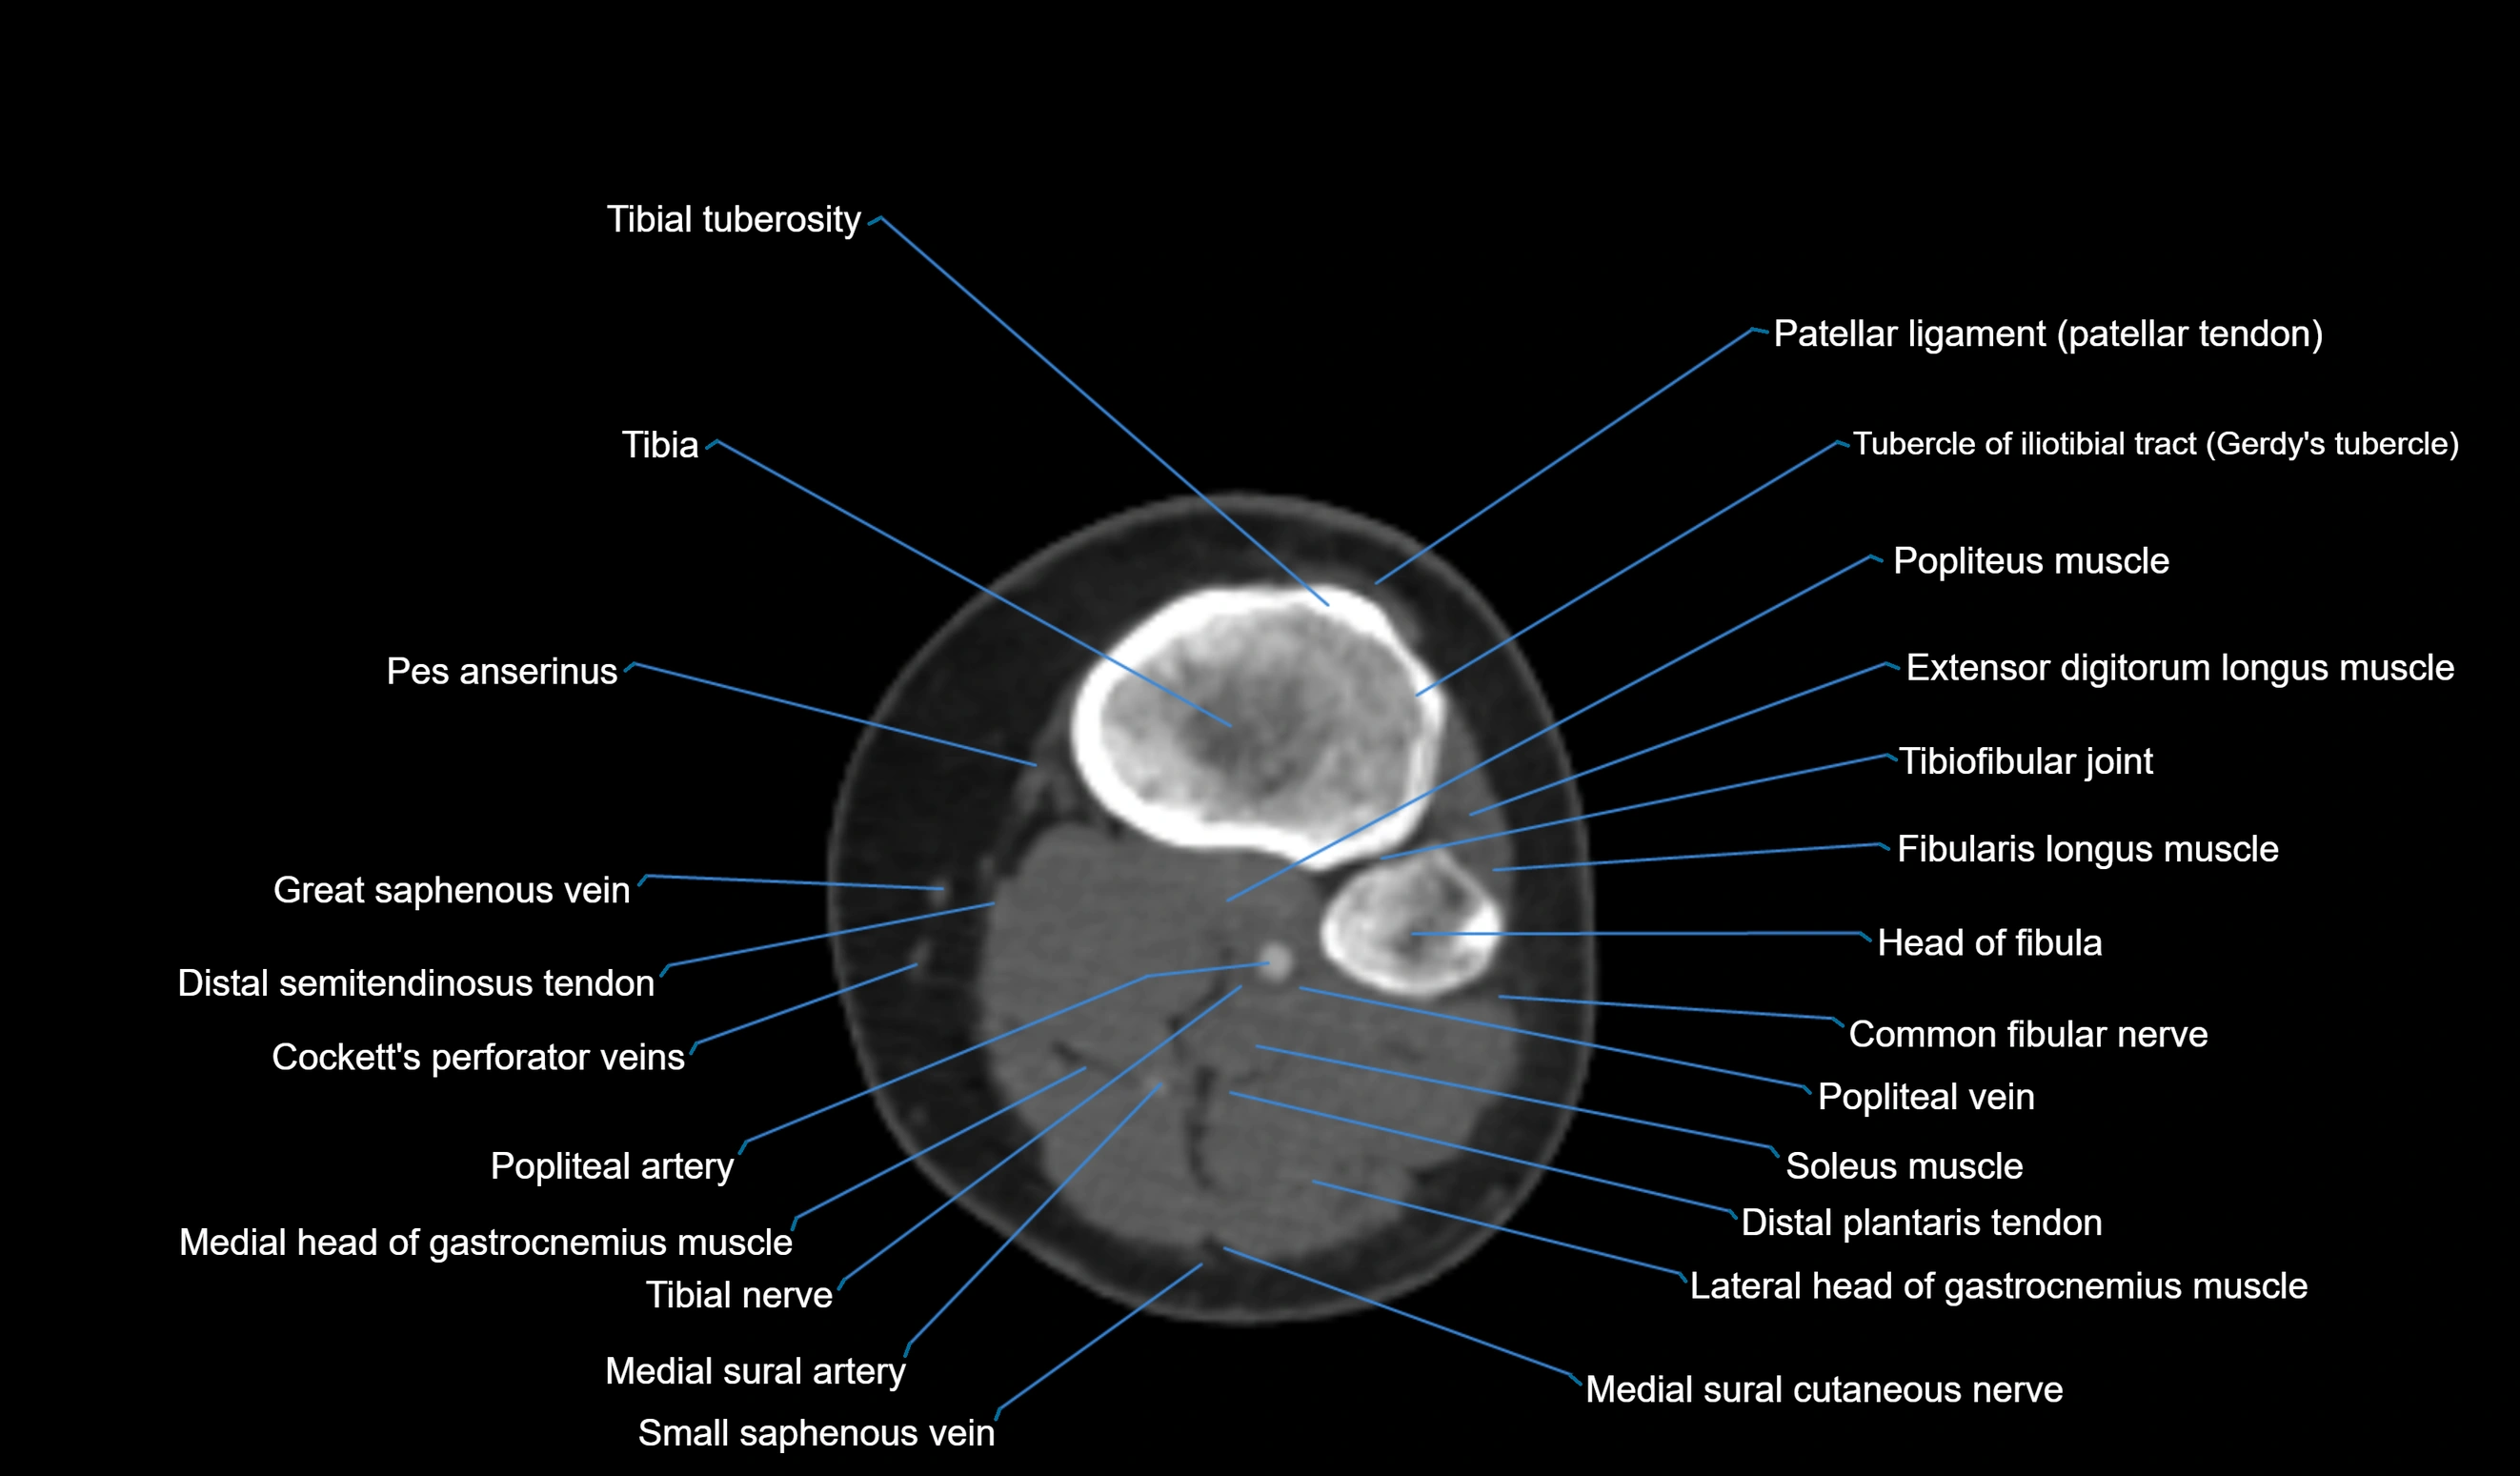

- Tibial tuberosity

- Tibia

- Patellar tendon (patellar ligament)

- Tubercle of iliotibial tract

- Popliteus muscle

- Extensor digitorum longus muscle

- Superior tibiofibular joint

- Fibularis longus muscle (peroneus longus muscle)

- Head of fibula

- Common fibular nerve

- Popliteal vein

- Soleus muscle

- Plantaris muscle

- Medial head of gastrocnemius muscle

- Lateral head of gastrocnemius muscle

- Medial sural cutaneous nerve

- Small saphenous vein

- Popliteal artery

- Tibial nerve